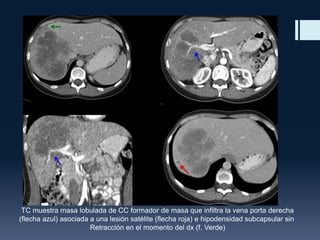

TC muestra masa lobulada de CC formador de masa que infiltra la vena porta derecha

(flecha azul) asociada a una lesión satélite (flecha roja) e hipodensidad subcapsular sin

Retracción en el momento del dx (f. Verde)

TC muestra masalobulada de CC formador de masa que infiltra la vena porta derecha (flecha azul) asociada a una lesión satélite (flecha roja) e hipodensidad subcapsular sin Retracción en el momento del dx (f. Verde)